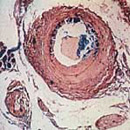

Bildunterschrift: Cholesterin-Ablagerungen in einer Arterie (Bild 1) und Fettzellen im Körper (Bild 2).

Bildquelle: Karl-Franzens-Universität Graz